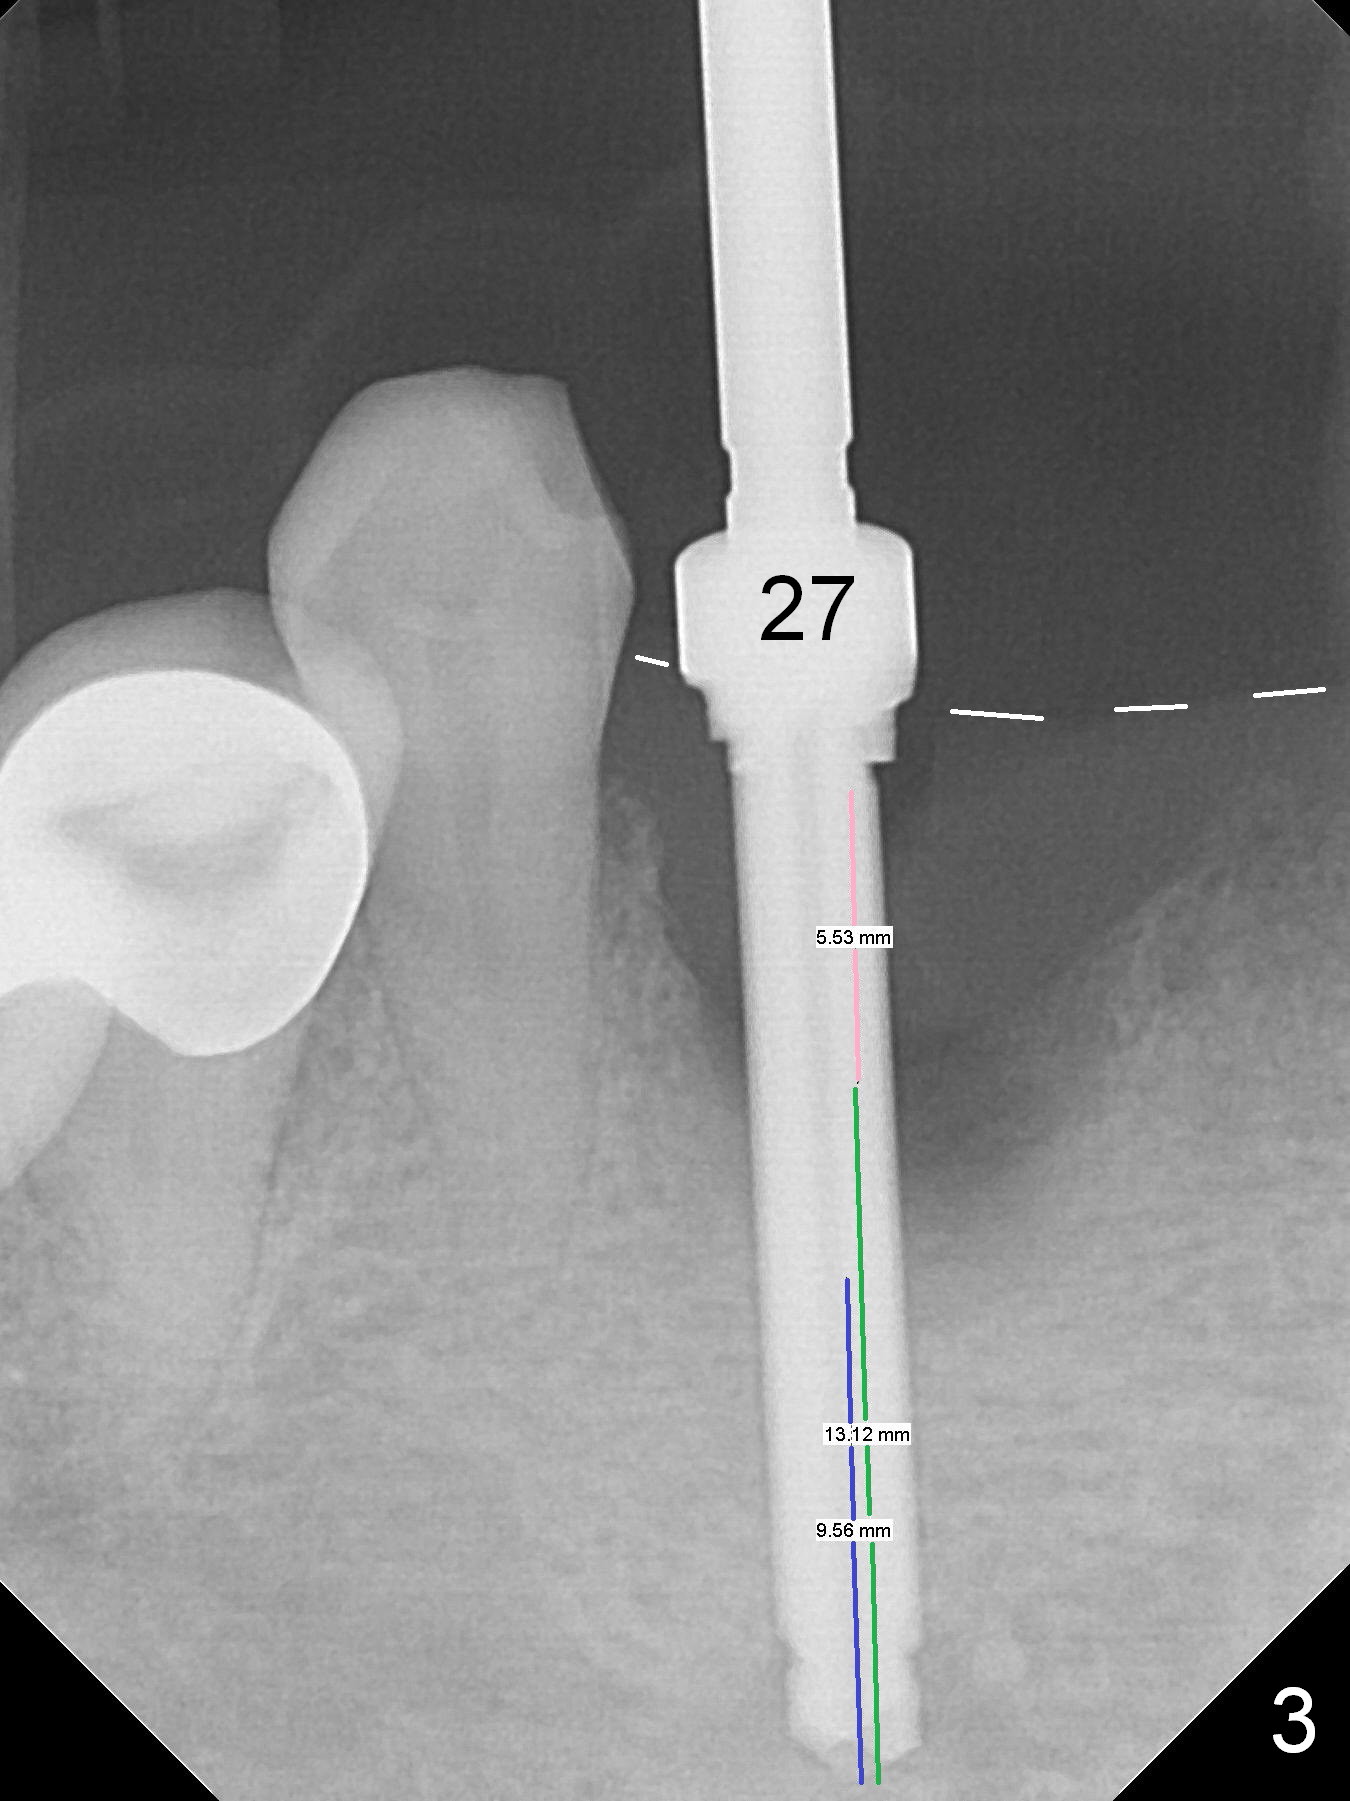

There is severe buccal gingival recession at #27 (Fig.1 arrow), as compared to that at #22. After removing the bridge and extraction of #27 (Fig.2 with severe loss of the buccal plate), a 3x18 mm drill is used to finish osteotomy (Fig.3). A 3.8x13 mm UF implant (Fig.3 green line) will be placed with 9 mm in the apparently solid, native (new) bone (blue line), while the coronal 5 mm will be occupied by the 5 mm cuff of a cemented abutment (pink line). The white dashed line is the gingival margin. The osteotomy is initiated as lingual as possible so that there will be at least 2 mm buccal gap when the narrow implant is placed. In spite of effort and precaution (guided surgery could control the trajetory), the coronal end of the implant tilts buccally so that a 4.5 mm 15 ° A 4 mm angled abutment is placed slightly subgingival (except buccal; Fig.5 A).